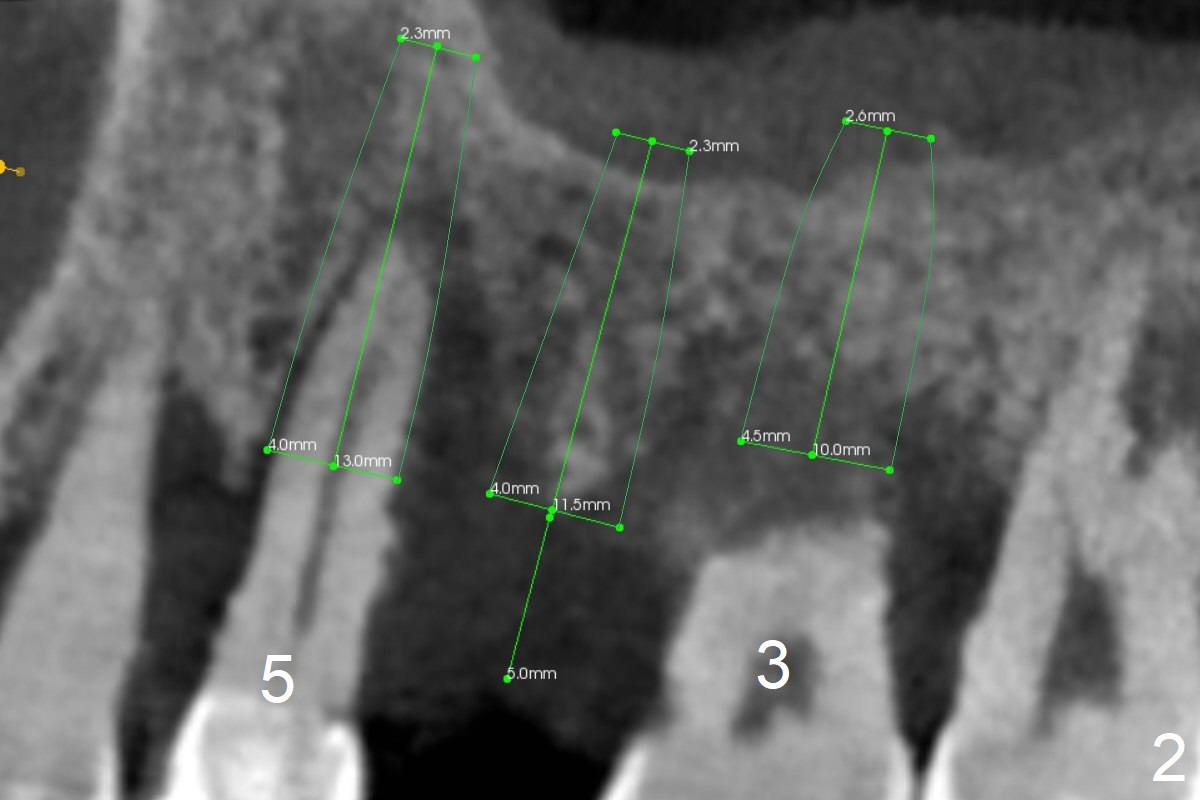

A 36-year-old man with chronic periodontitis will return for #3 and 5 extraction and FPD (Fig.1,2). The initial depth of the septum of #3 will be <8.5 mm (Fig.3). The septum seems narrow; bone expansion will be done with DIO bone expander kit. The osteotomy at #5 will be in the palatal socket (Fig.4 P). Take photos for Lower Anterior provisional.